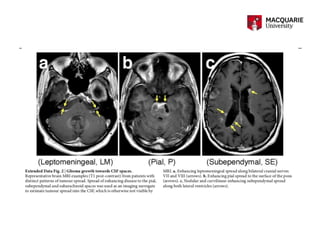

• #11 Shedding of tumour DNA was associated with tumour progression, tumour burden and spread towards the ventricular system or SAS Similar to another study demonstrating tumours abutting a csf reservoir or cortical surface being more likely to shed tumour DNA

• #12 Glioma growth towards CSF spaces Shedding of tumour DNA was associated with tumour progression, tumour burden and spread towards the ventricular system or SAS Similar to another study demonstrating tumours abutting a csf reservoir or cortical surface being more likely to shed tumour DNA

• #16  Frequency of shared vs tissue only or csf only mutations in matched tumour tissue-csf sample pairs 30 tumour pairs without DNA hypermutation Median 81.7% shared mutation range (0-100%) a. Demontsrating shared vs tissue or CSF only mutations matched tumour tissue - without DNA hypermutaiont In patients with hypermutated tumours shared mutations were considerably less comman 3-49% Median 19.6% Nb. With DNA hypermutation Comparison between clonal and subclonal with clonal tumour mutations The majority fo mutations that were clonal in tissue were also present in csf even in patients with DNA hypermutatin Subclonal mutations were less lilkey to be shared (2c) d, CSF ctDNA results from contemporaneously collected CSF replicates. Five patients underwent two CSF collections within three weeks (one lumbar puncture (LP) and one ventricular sample collected during ventriculo-peritoneal (VP) shunt placement). Heat maps display the variant allele frequencies of all the mutations detected in either replicate. e. Comparison of tumour – csf pairs colleted withitn a three week period Tumour samples via bx and CSF via LP  demonsdtrate variant allele frerquencies fo all the mutations present in either sample f. Divergence of mutations in growth factor receptor pathway Concordance between contemporaneously collected CSF replicatses and tumour –csf pairs 6 patients in the study underwent placement of VPS for hydrocpehalus withint 3 weeks of intiial LP CSF replicates were highly concordant Near identical As interval between tumour and csf collection increasd greater divergence f genetic profile esp for gene encoding memberes fo GF signalling patwhays 2f. 5 patients had a tumour resection within 3 weeks fo CSF collection and showed near identiftical genetic profiles in csf and tumour tissue 2e As the interval between tumour and csf collection increasd therer was greater divergence of the genetic profiles in particular for genes encoding members of growth factor signalling pathwyas *2f) Our study shows that tumour-derived DNA in CSF from patients with glioma provides a comprehensive and genetically faithful rep- resentation of the tumour genome at the time of the CSF collection. The frequency and type of alterations in the CSF closely resembled the genomic landscape of diffuse glioma, as defined in large oncogenomic studies2,1, and we observed high concordance between CSF and tumour DNA in patients who underwent both lumbar puncture and neurosurgical tumour resection within a few weeks. . Any divergence between CSF and tumour genomes within the same patient followed the pattern of genomic evolution that has been reported in studies of sequential tumour biopsies. This evolution is characterized by the per- sistence of truncal genetic alterations (IDH1, 1p/19q codeletion, TP53, TERT, ATRX) and by convergent and branched evolution within glioma core pathways, in particular growth factor receptor pathways3–1